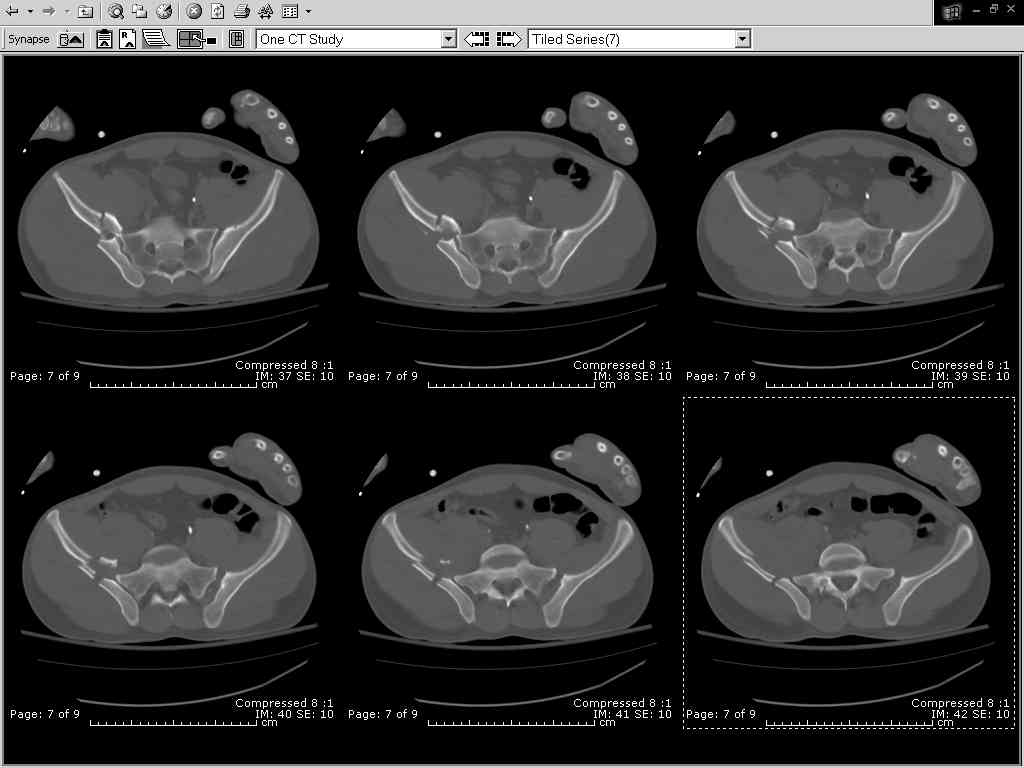

Fluoroed L SI joint and it seemed stable, but wide. So, applied c-clamp to try to squeeze down L SI joint (and note, on the last slide attached, that it's still wide), and got it closer. Single perc Iliosacral screw 40mm thread.

So, there I was with the aforementioned info on my mind, and my R iliac wing was a little malreduced. I think it's in residual extension and some external rotation, explaining the 5-6mm gap/step

on the posterior R iliac wing. (When I loooked at the inlet fluoro, the L obturator foramen was more visible than the R obt foramen, as was the R ischial spine) so it's not as stable as if it were

anatomic, despite all the metal. This came from hesitance to take down all the posterior paraspinals to really see the R posterior crest (where the malreduction is best seen on the iliac oblique view), and I could see the entire iliac fossa and most of the crest anyway.

Finally, the L SI joint seemed wide, even after closing it with c-clamp and iliosacral screw, so I added the extra 4 hole symphyseal plate anteriorly (even though to my knowledge unproven). That was the thinking and sequence of events that lead to the 2 symph plates shown. Note that the 4 hole recon is a locking plate (non-locked in medial 2 holes before locked screws in holes 1 & 4) -- fertile ground for debate on that I'm sure!